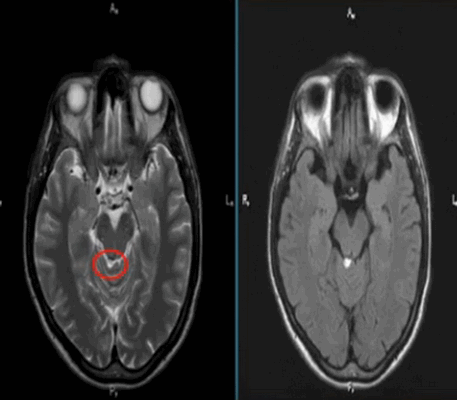

Липома четверохолмной цистерны на МРТ (обведена кругом)

Абсцесс головного мозга на МРТ (указан стрелкой)

Лакунарный инфаркт головного мозга на МРТ (указан стрелкой)